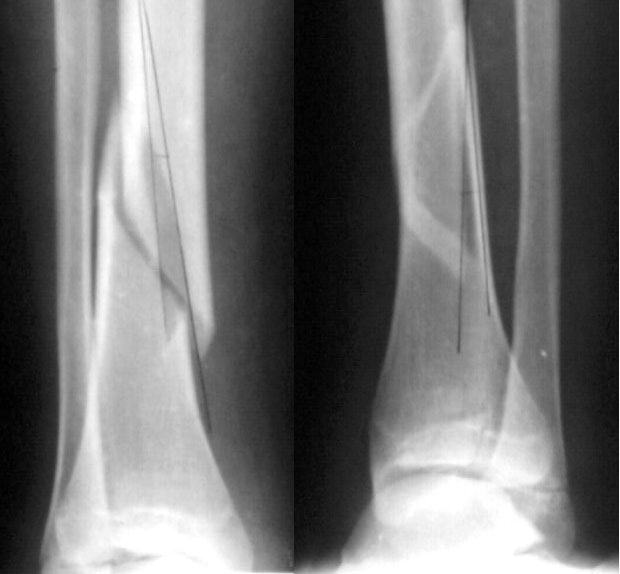

A female 14 y.o. sustained a spiral fracture of the distal tibia 1.5 years ago (Image 1). She was treated elsewhere by closed retrograde nailing with a thin nail (Image 2). The nail was removed after healing.

Image 1